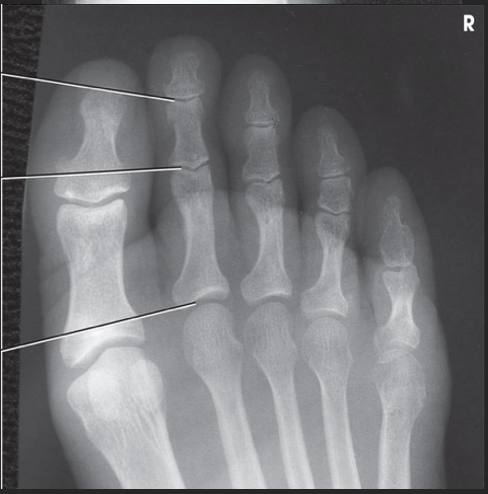

Name this projection.

AP oblique toes

State the degree and type of rotation used.

Medial rotation 30-45 degrees

Which aspect of the foot rests on the IR?

Medial aspect

Where does the CR enter?

Perpendicular to 3rd MTP joint

When radiographing the 1st-2nd toes, which oblique should be used?

Medial (rotate on medial/unaffected side)

When radiographing the 4th-5th toes, which oblique should be used?

Lateral (rotate on lateral/affected side)